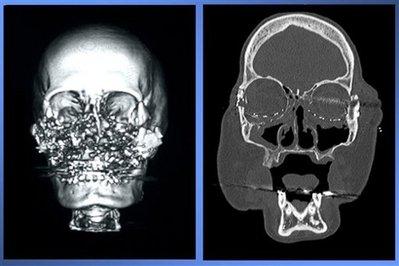

Сначала женщине восстановили кости лица: из ребер были воссозданы скулы, а кости ног послужили материалом для верхней челюсти.

Затем, 22 декабря 2008 года, в ходе 22-часовой операции доктор Мария Семенов (Maria Siemionow) пересадила Конни мышцы, кровеносные сосуды и кожу с лица только что умершей женщины. Всего врачи восстановили 80% лица пострадавшей.